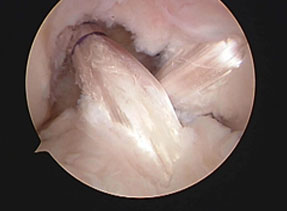

前十字・後十字靭帯同時再建

複合靭帯再建術のイメージ